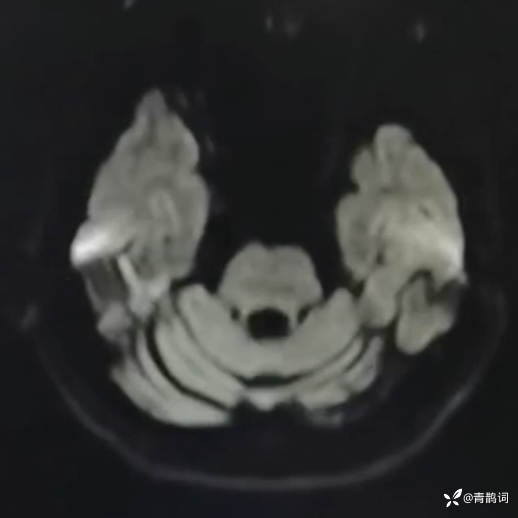

乐痴于医等 2人推荐简要病史:42岁男性,记忆力下降及听力下降一年余。既往体健,否认前驱感染病史。否认家族史。三个月前就诊于当地医院,自述腰穿脑脊液乳酸增高。现就诊于我院,查体记忆力下降,计算力下降,定时定向差,吟诗样语言。完善磁共振如下:

DWI:

2.患者小脑萎缩严重,和大脑半球的病灶之间有无关系?能否用一元论解释?